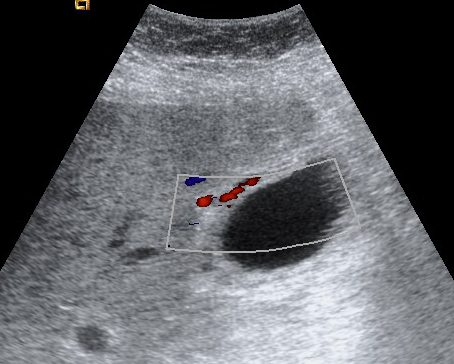

Se realiza ecografía abdominal:

En sucesivos cortes observamos lo siguiente:

Se observa una mala evolución radiológica. Dada la clínica del paciente y los hallazgos ecográficos podemos concluir que estos hallazgos son compatibles una colecistitis xantunogranulomatosa litiásica sobreinfectada (que se confirmó posteriormente con anatomía patológica).

Se procedió a realizar colecistotomía por US que evidenció la salida de pus y posteriormente se ingresó el paciente en la UCI.

- Colecistitis xantunogranulomatosa: nódulos o bandas intramurales. Se producen por la oclusión de los senos de Rokitansky Aschoff de la pared, los cuales se rompen, luego la bilis coloniza la pared y finalmente produce una reacción inflamatoria a la que puede sobreañadirse una infección. Es un factor de riesgo para el carcinoma.

- Eco y TC: Litiasis + engrosamiento mural focal o difuso. Puede haber cambios inflamatorios pericolecísiticos. Los nódulos hipocogénicos o bandas pueden sugerir el diagnóstico específico de c. xantunogranulomatosa.

- El diagnóstico raramente se realiza previo a la cirugía y al análisis histopatologíco.